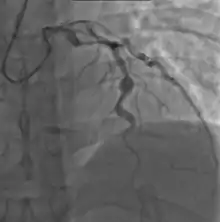

Heart complications are the most important aspect of Kawasaki disease, which is the leading cause of heart disease acquired in childhood in the United States and Japan.[30] In developed nations, it appears to have replaced acute rheumatic fever as the most common cause of acquired heart disease in children.[14] Coronary artery aneurysms occur as a sequela of the vasculitis in 20–25% of untreated children.[51] It is first detected at a mean of 10 days of illness and the peak frequency of coronary artery dilation or aneurysms occurs within four weeks of onset.[47] Aneurysms are classified into small (internal diameter of vessel wall <5 mm), medium (diameter ranging from 5–8 mm), and giant (diameter > 8 mm).[30] Saccular and fusiform aneurysms usually develop between 18 and 25 days after the onset of illness.[14]

Even when treated with high-dose IVIG regimens within the first 10 days of illness, 5% of children with Kawasaki disease develop at the least transient coronary artery dilation and 1% develop giant aneurysms.[52][53][54] Death can occur either due to myocardial infarction secondary to blood clot formation in a coronary artery aneurysm or to rupture of a large coronary artery aneurysm. Death is most common two to 12 weeks after the onset of illness.[14]

Many risk factors predicting coronary artery aneurysms have been identified,[20] including persistent fever after IVIG therapy,[55][56] low hemoglobin concentrations, low albumin concentrations, high white-blood-cell count, high band count, high CRP concentrations, male sex, and age less than one year.[57] Coronary artery lesions resulting from Kawasaki disease change dynamically with time.[3] Resolution one to two years after the onset of the disease has been observed in half of vessels with coronary aneurysms.[58][59] Narrowing of the coronary artery, which occurs as a result of the healing process of the vessel wall, often leads to significant obstruction of the blood vessel and the heart not receiving enough blood and oxygen.[58] This can eventually lead to heart muscle tissue death, i.e., myocardial infarction (MI).[58]

- Angiography was historically used to detect coronary artery aneurysms, and remains the gold standard for their detection, but is rarely used today unless coronary artery aneurysms have already been detected by echocardiography.